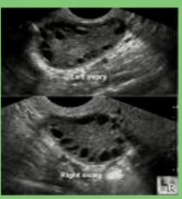

Ultrasound: pearls on a string